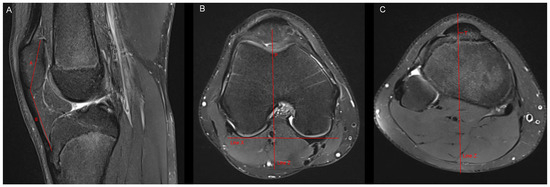

Figure 2. Measurement of the patella tilt angle, the bony sulcus angle and the cartilaginous sulcus angle. (A) In accordance with Grelsamer et al. [10], the patella tilt angle (alpha) was defined as the subtended by a line joining the medial and lateral edges of the patella and a horizontal line measured in the axial slice with the largest mediolateral diameter of the patella. (B) The bony sulcus angle was defined as the angle between the bony medial and lateral facets. (C) The cartilaginous sulcus angle was defined as the angle between the cartilaginous medial and lateral facets.